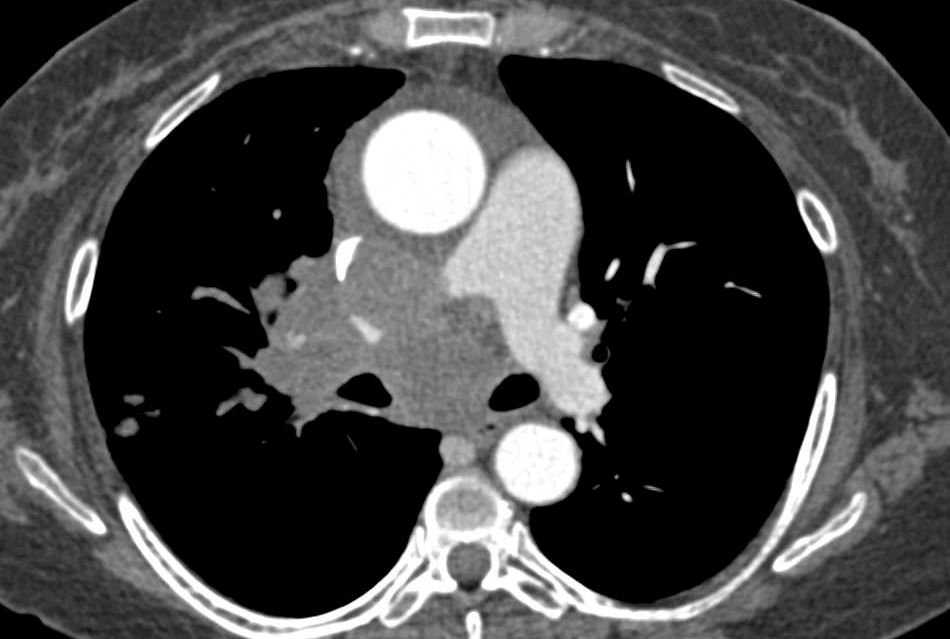

STRÅLING: Skanning med CT-maskiner har vært ansett som sikre, fordi de forårsaker få synlige skader på arvestoffet, og er derfor mye brukt. Men en undersøkelse ved Universitetet i Cambridge viser at selv den lave strålingsdosen man får ved CT-skanning, hjelper potensielle kreftceller i konkurransen mot friske celler. Og vi har alle slike celler i kroppen. Denne uheldige bieffekten kan imidlertid motvirkes ved å gi pasientene en antioksidant – N-Acetyl Cystein (NAC) – før de utsettes for stråling (Cell Stem Cell). BV